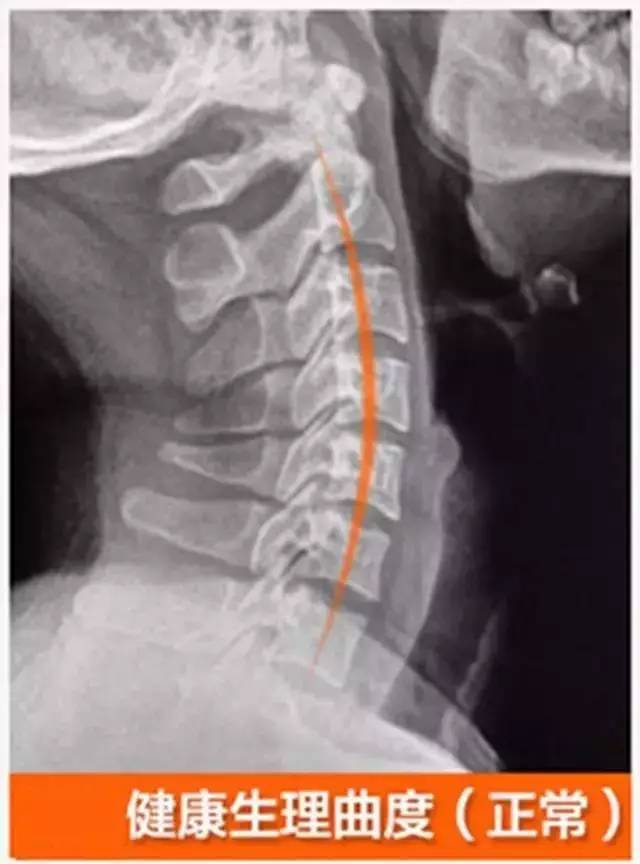

颈椎生理曲度变直如何恢复?

正常人颈椎生理曲度

正常人的颈椎曲度图片

人体正常颈椎曲度图片